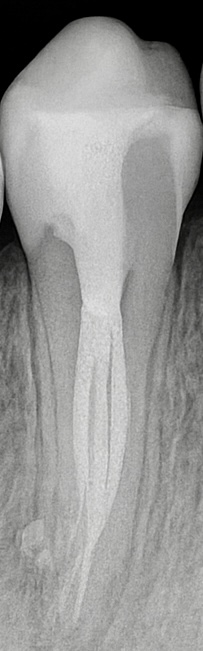

The patient presented with deep caries and pain localized to the maxillary second premolar (Fig 1). Cold testing elicited lingering pain, confirming symptomatic irreversible pulpitis. CBCT imaging revealed a 1:3 canal configuration—one orifice splitting into three canals apically, emphasizing the need for magnification and careful instrumentation.

All canals were negotiated with #10 K-files and confirmed patent. Electronic apex locator (Root ZX II) and radiographs established the working length (Fig 3). Canal configuration confirmed as one coronal entry dividing into mesiobuccal, distobuccal, and palatal apical exits.

The post-op radiograph showed dense, continuous obturation in all three canals with well-defined apical seals (Fig 7). The final restoration demonstrated perfect occlusal harmony and marginal adaptation.

- Fig 3: Working length confirmation with three canal paths visible.

- Fig 7: Final post-operative radiograph confirming 1:3 canal configuration and apical seal.